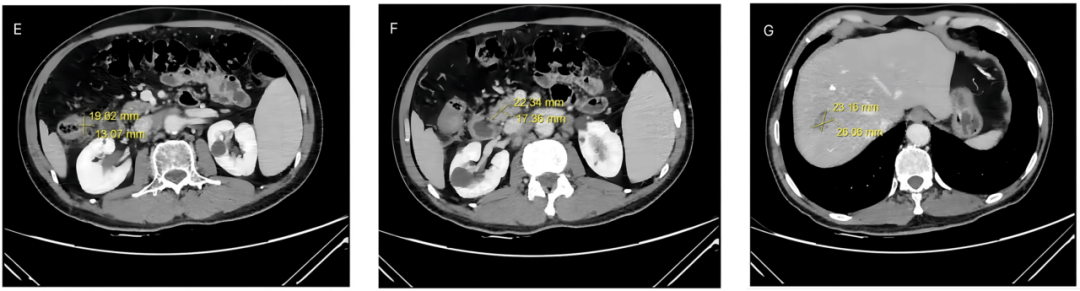

• 肿瘤大小显著缩小:结肠原发肿瘤从 3.7cm×3.1cm 缩小至 2.0cm×1.3cm,腹膜后淋巴结转移灶从 5.2cm×4.3cm 缩小至 2.2cm×1.7cm,肝转移灶从 3.9cm×3.2cm 缩小至 2.6cm×2.3cm,达到部分缓解(PR)标准。

E:结肠肿瘤CT图   F:淋巴肿瘤CT图   G:肝脏肿瘤CT图